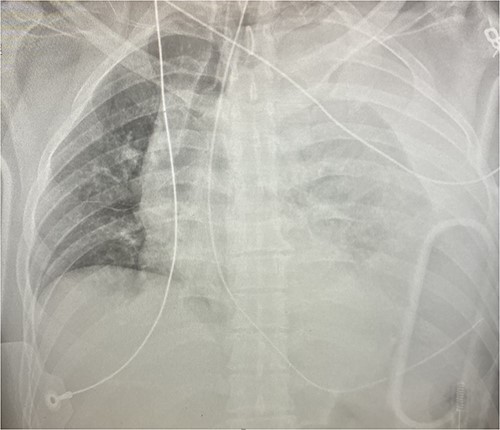

An approximately 40-year-old male was involved in a motor vehicle collision after hitting a concrete wall at highway speeds. The patient was found to have a Glasgow Coma Scale (GCS) score of 3 on scene, so he was intubated and brought to the trauma center as a level I trauma activation via helicopter. Upon arrival, his primary survey was significant for an airway secured with an endotracheal tube, tachycardic to the 110 s, hypotensive with a systolic in the 60s and GCS of 3 T. His secondary survey identified an open mandibular fracture, right hip dislocation and an obvious left thigh deformity with palpable distal pulses. His chest x-ray revealed a left hemothorax (see Fig. 1), his pelvic-x-ray confirmed the hip dislocation, and his Focused Assessment with Sonography for Trauma (FAST) examination was negative for free fluid in all four windows. A left thoracostomy tube was immediately placed, which evacuated 500 cc of blood with minimal continuous output. He was given 1 unit of packed red blood cells (PRBC) with blood pressure normalization but persistent tachycardia.

Given his hemodynamic normalization without ongoing transfusion requirements, he was taken to the computed tomography (CT) scanner for axial imaging of the head, chest, abdomen and pelvis. A CT angiogram of the chest revealed trace pneumopericardium and pneumomediastinum with trace hemopericardium. A 1.7 × 0.7 cm out-pouching at the anterior aspect of the right ventricular apex concerning for a traumatic pseudoaneurysm was also detected (see Figs 2 and 3). His other injuries were notable for subarachnoid and subdural hemorrhages, left temporal bone fracture, open mandibular fracture, left 3–6th, 10th and 11th rib fractures, a 4th lumbar vertebrae burst fracture with 1st and 3rd lumbar vertebrae compression fractures, 8–11th thoracic vertebrae compression fractures, and a left femoral neck fracture. He was subsequently transferred back to the trauma bay where a formal trans-thoracic echocardiogram was immediately performed, which demonstrated a dyskinetic area of the right ventricular apex with paradoxical out-pouching during systole—suggestive of pseudoaneurysm and confirming the diagnosis on axial imaging.

Axial CT imaging demonstrating pseudoaneurysm of right ventricular free wall rupture.

Sagittal CT imaging demonstrating pseudoaneurysm of right ventricular free wall rupture.